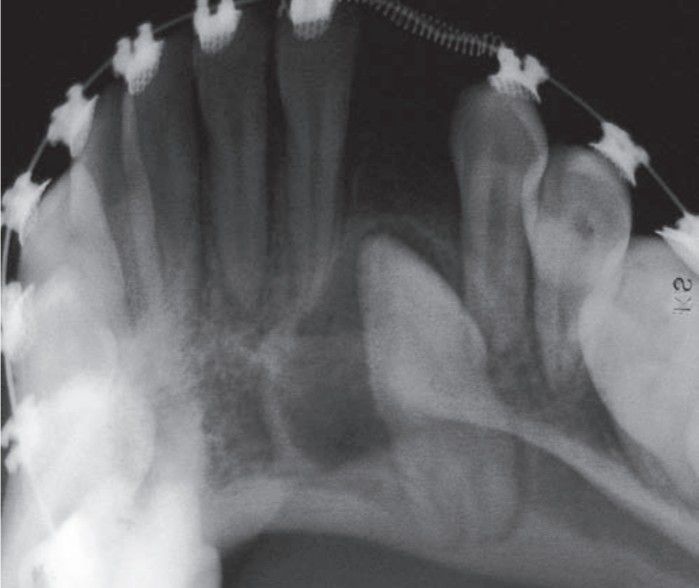

Adenomatoid odontogenic tumor xray

Adenomatoid odontogenic tumor surrounding crown of an impacted anterior tooth